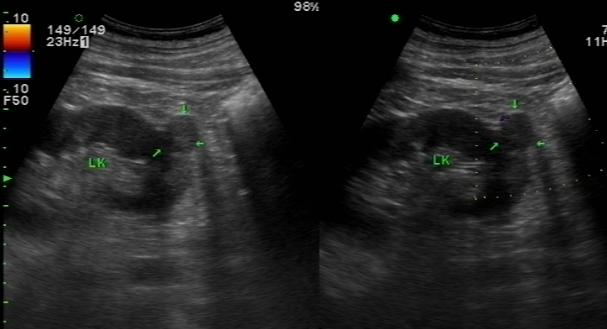

肾脏透明细胞癌